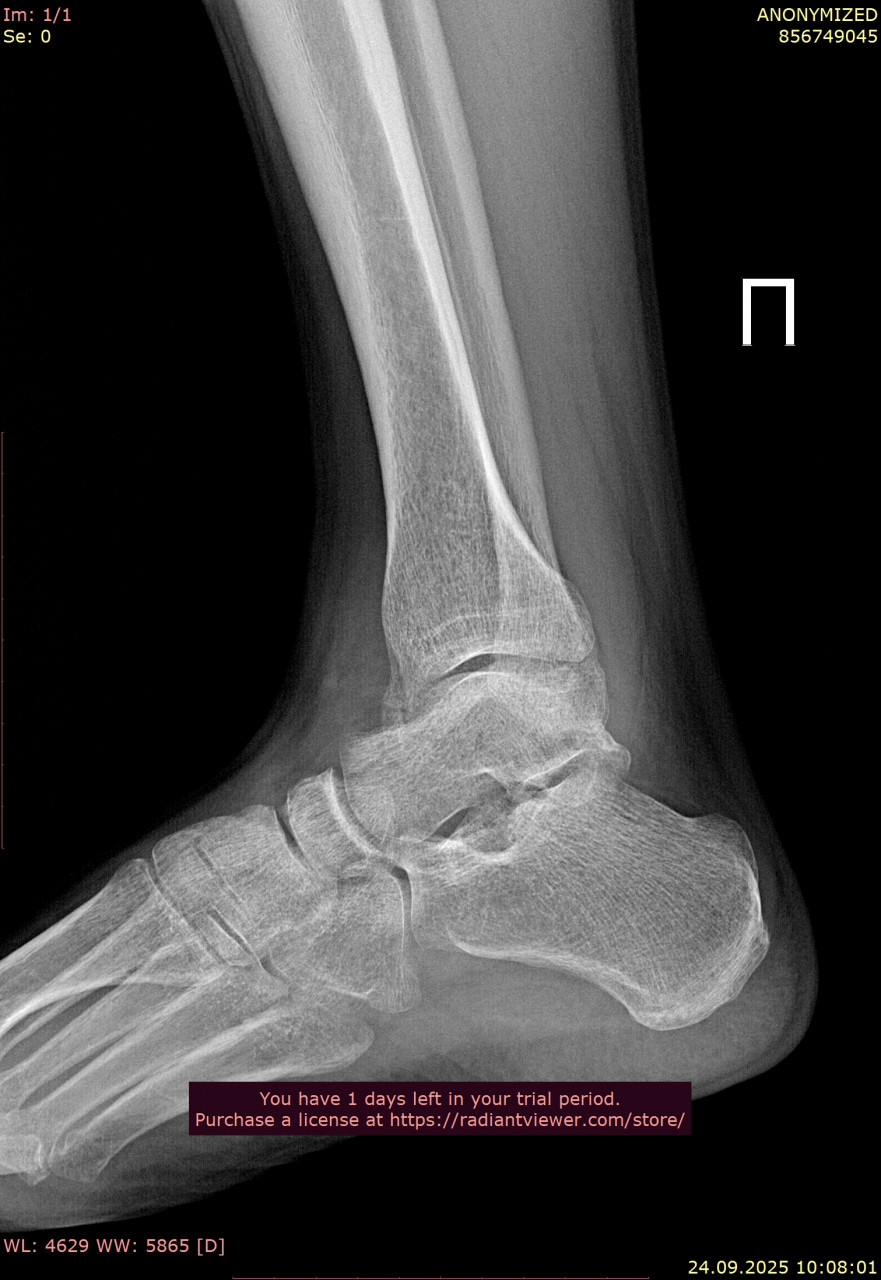

Посмотрите, пожалуйста, снимки голеностопного сустава от 23.06.2025, когда был перелом, и спустя 3 месяца от 24.09.2025. Как Вы считаете, полностью ли восстановился голеностопный сустав, артроз обязательно приведет к болям при ходьбе в ближайшие годы, можно ли этого избежать? Ведь до пенсии теперь еще далеко( Сейчас собираюсь подбирать ортопедические стельки, может посоветуете как это сделать подешевле, из за длительной нетрудоспособности денег почти нет. Смог прикрепить только одну проекцию от дыты переломаб еще есть снимки стопы, там перелом плюсневых.

Здравствуйте. На контрольных снимках костная структура выглядит восстановленной, консолидация произошла, признаков грубых осложнений нет. Артроз после таких травм возможен, но при отсутствии боли и отёка риск выраженных проблем в ближайшие годы невелик, особенно если продолжать ЛФК и постепенно наращивать нагрузку. Стельки лучше подбирать индивидуально, даже самые простые готовые варианты из аптек или ортопедических салонов могут помочь и стоят дешевле индивидуальных.